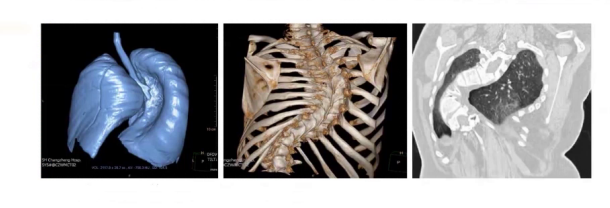

实验室检查血常规、血生化、凝血功能和血气基本正常,心脏超声提示心脏无器质性功能异常,胸部CT显示呈桶状胸,前后径大于10左右,其余无明显异常,3D打印提示自胸3至腰3椎体后柱及融合椎体畸形,胸主动脉磁共振提示胸腰段脊髓明显受压。